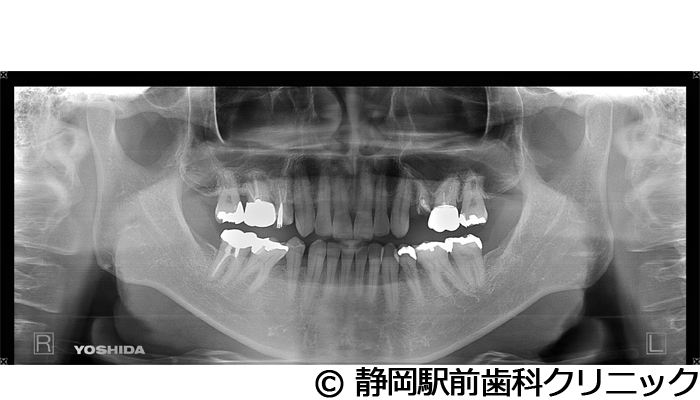

【症例3】右下インプラント埋入

- 治療前

- 治療後

- 治療名

- 右下インプラント埋入

- 費用

- 440,000円(税込)

- 期間

- 6ヵ月

治療内容

-

患者様の症状

右下の歯が折れてしまい、食べにくいため、インプラント治療希望。

治療方法

右下2本は抜歯を行い、骨の治癒後にCTを撮影し、詳細に治療計画を立案しました。その後、インプラントを埋入し、人工歯を被せて咬合の回復を行いました。

治療結果

患者様からは右でも好きな物を食べることができるようになり、喜んでいただきました。人工歯はセラミックにて作成し、見た目もご満足いただけました。

※治療結果は個人差があります。

治療を行う上での注意点(リスク・副作用)

術後は、出血、腫れ、痛みなどが出る可能性があります。